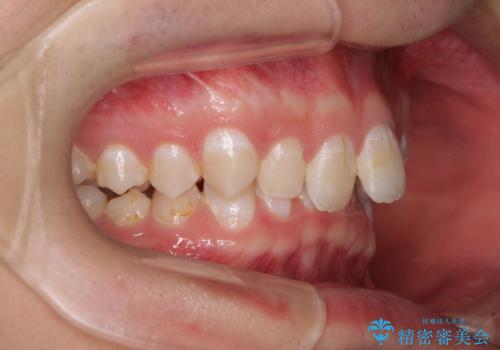

下顎前歯が全て隠れてしまうほどの深い咬合で、左右の奥歯は1歯対1歯で咬み合う状態でした。

前方に移動している上顎臼歯を補助装置にて遠心移動させることで1歯対2歯の臼歯咬合を目指し、同時に深い咬合を改善していくこととしました。